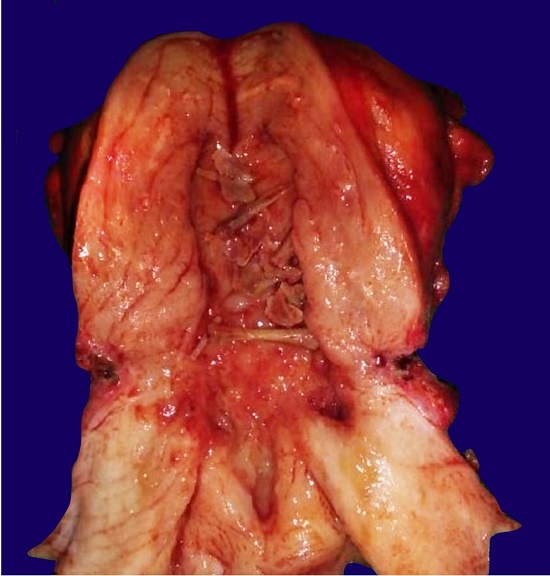

The endometrial stroma showed a florid chronic inflammation predominantly composed of plasma cells and a few lymphocytes. Therefore, the report of chronic endometritis with osseous metaplasia was rendered. After a few days, we received the same patient’s hysterectomy specimen, which showed intrauterine bones in the endometrial cavity (Figure 3).